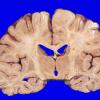

1A Paraneoplastic anti-Hu (Case 1) gross 1